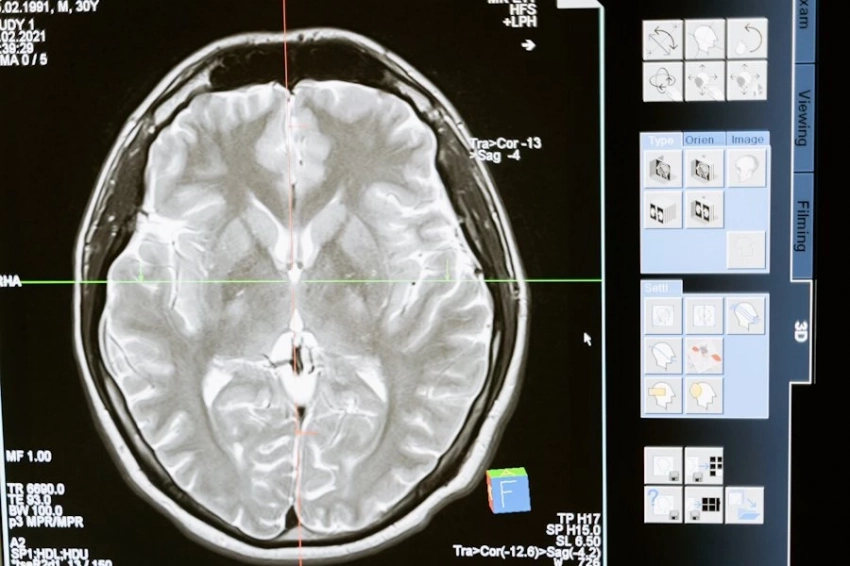

Исследователи из Пенсильванского университета сделали значительный шаг вперед в борьбе с одной из наиболее агрессивных форм опухолей мозга — глиобластомой. Они представили новую методику, основанную на усовершенствованной технологии CAR-T терапии, которая нацеливается сразу на два опухолевых антигена — EGFR и IL13Rα2. Это нововведение позволяет значительно повысить точность и эффективность воздействия на злокачественные клетки, что является критически важным в лечении такой сложной болезни.

Одним из ключевых отличий новой методики является способ введения модифицированных иммунных клеток. В отличие от традиционных подходов, клетки доставляются непосредственно в спинномозговую жидкость, что обеспечивает более тесный контакт с опухолью и, как следствие, улучшает результаты лечения. Это обстоятельство подчеркивает значимость прямого взаимодействия терапевтических агентов с опухолевыми клетками, что может существенно повысить шансы на успех.